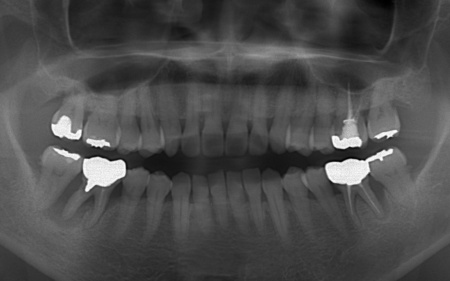

下左右の第1大臼歯を抜歯し、その部位にインプラントを埋め込む手術を行いました。同時に、インプラントの隣にある下の第2大臼歯に対して歯周組織再生療法を施しています。

さらにインプラントの周囲には角化歯肉移植を行いました。これは患者様のお口の中から歯ぐきを採取して移植する方法で、汚れが溜まりにくく清掃しやすい歯ぐきの状態をつくります。

上左右の奥歯についても歯周組織再生療法を行い、歯をできるだけ残せるよう治療を進めました。

また、左上の奥歯は虫歯を取り除いたあと、歯の形を整えて型取りを行い、最終的にジルコニアクラウンを装着しています。

段階的に治療を進め、すべての治療を終了しました。

歯周組織再生療法4ヶ所、インプラント2本、角化歯肉移植、ジルコニアクラウン